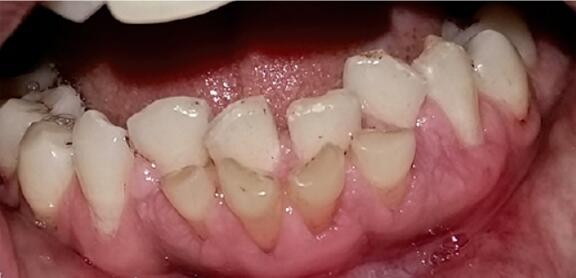

这是个俗语,通常是指恒牙长出来后,乳牙还不脱落,形成前后两排牙齿的表现,如下图所示。

图片来自参考文献[1]

大家能看出来哪些是恒牙吗?哈哈,当然是里面那两颗大的下切牙,从数量也能看出,在换牙时,乳牙数量肯定是比恒牙多的。

对于这种双排牙,最常见的是下切牙,也就是上面图片中所示的。